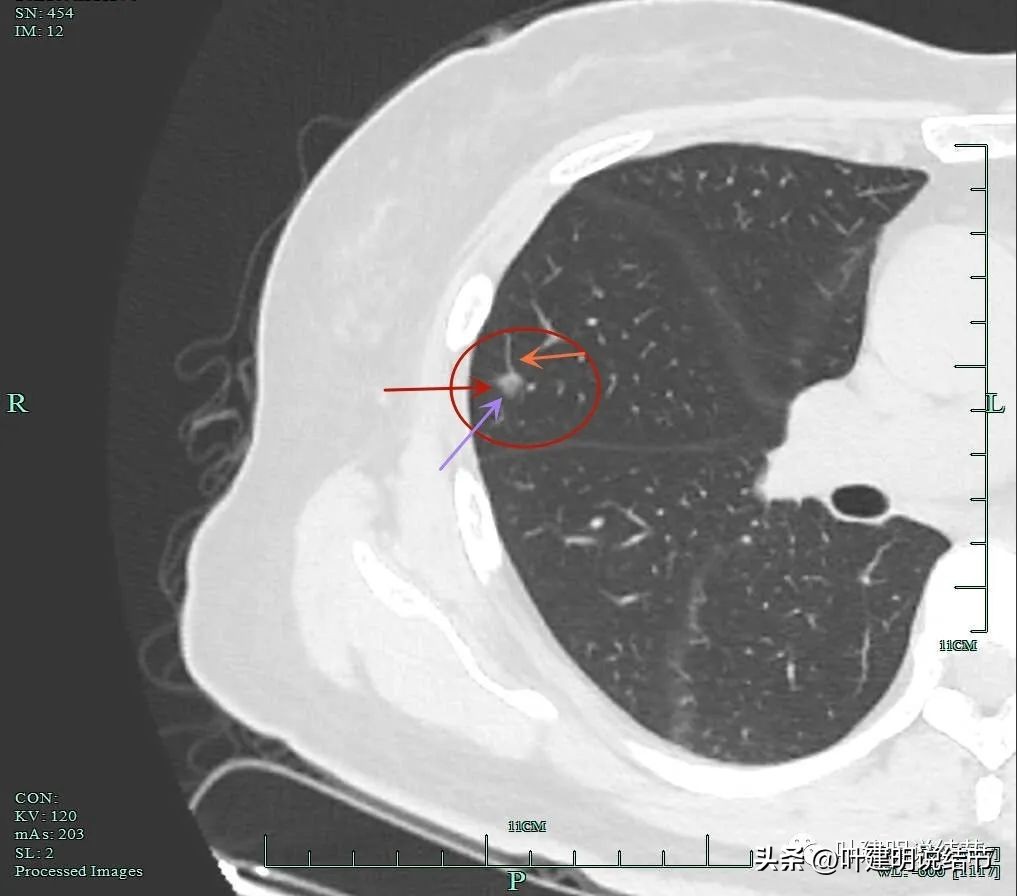

靶扫描重建图像显示了病灶明显的血管进入(如桔色箭头所示),灶内似见进入血管的穿行,而且显得毛糙与异常增粗。

微小血管进入明显且多处;粉色箭头示病灶内部偏实性成分也明显。

血管征以及磨玻璃成分,病灶轮廓与瘤肺边界清。我们见进入的这支血管是有异常增粗的,它不是越往远心端越细,而且基本同样粗细走向病灶,到了病灶内部后显得散开来,密度反而更显高点。

灶内明显增粗毛糙的血管走行,磨玻璃成分轮廓清。